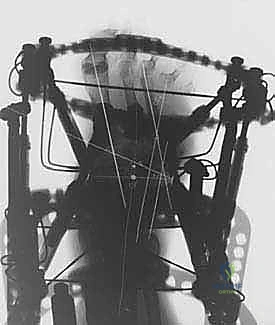

لتجاوز كل العيوب القاتلة للجراحات التقليدية، يبرز تفوق طريقة التصحيح التدريجي على مرحلتين التي يتقنها ويطبقها الأستاذ الدكتور محمد هطيف ببراعة منقطعة النظير. هذه الطريقة تعتمد على مبادئ الميكانيكا الحيوية المتقدمة (استخدام جهاز إليزاروف أو إطارات تايلور المكانية السداسية الأبعاد - Taylor Spatial Frame).

تسمح هذه التقنية بإعادة محاذاة دقيقة ومتحكم بها (مليمتر بمليمتر) للمفاصل المخلوعة أو المتفككة في قدم شاركو. من خلال التشتيت التدريجي (Gradual Distraction)، يتم شد الأنسجة الرخوة والأوعية الدموية والأعصاب ببطء شديد، مما يمنحها الوقت للتكيف والنمو دون أن تنقطع أو تتلف.

- تجميع الإطار: يتم توصيل هذه الأسلاك بحلقات خارجية معدنية أو كربونية تحيط بالساق والقدم (إطار إليزاروف). يتم تثبيت هذه الحلقات معاً بواسطة دعامات قابلة للتعديل.

3. مرحلة التصحيح التدريجي (Gradual Correction Phase)

تبدأ هذه المرحلة بعد أيام قليلة من الجراحة. يقوم المريض (أو مرافقه) بتدوير صواميل معينة على دعامات الجهاز الخارجي بمقدار محدد جداً (عادة 1 مليمتر في اليوم).

* هذا الشد البطيء يسحب العظام المنهارة لتعود إلى مكانها الطبيعي.

* يصحح التشوه دون التسبب في صدمة للأنسجة.

* يسمح بتكون أنسجة جديدة (Distraction Histiogenesis).

تستمر هذه المرحلة لعدة أسابيع حتى يتم الوصول إلى المحاذاة التشريحية المثالية واستعادة قوس القدم.